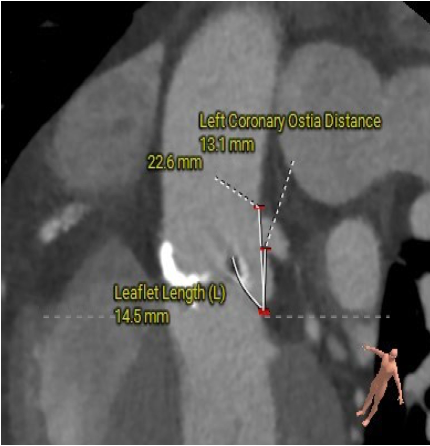

冠脉高度测量

LEFT CORONARY

左冠开口高度14.0mm

RIGHT CORONARY

右冠开口高度13.1mm

冠脉开口及瓣叶长度评估